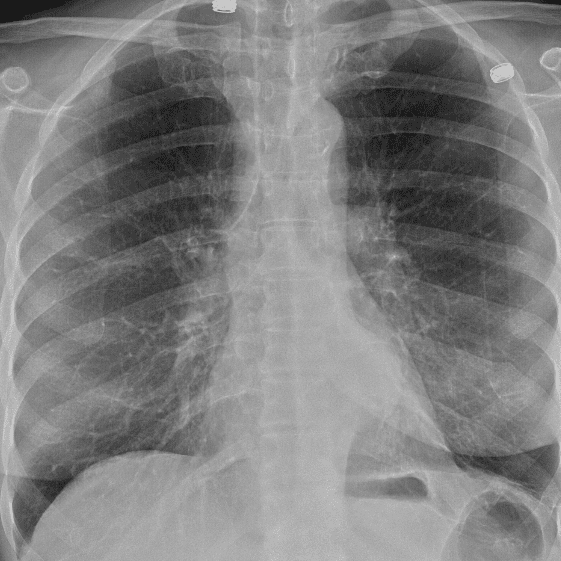

Practice Cases